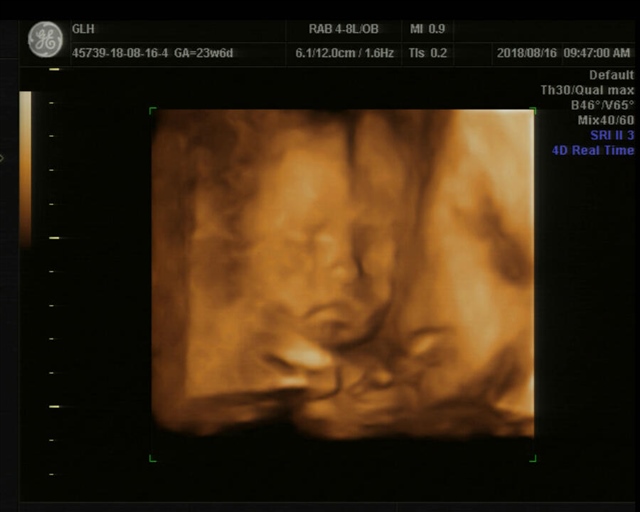

怀孕用户8lTW

孕24周+0天

你不给人家糖糖吃